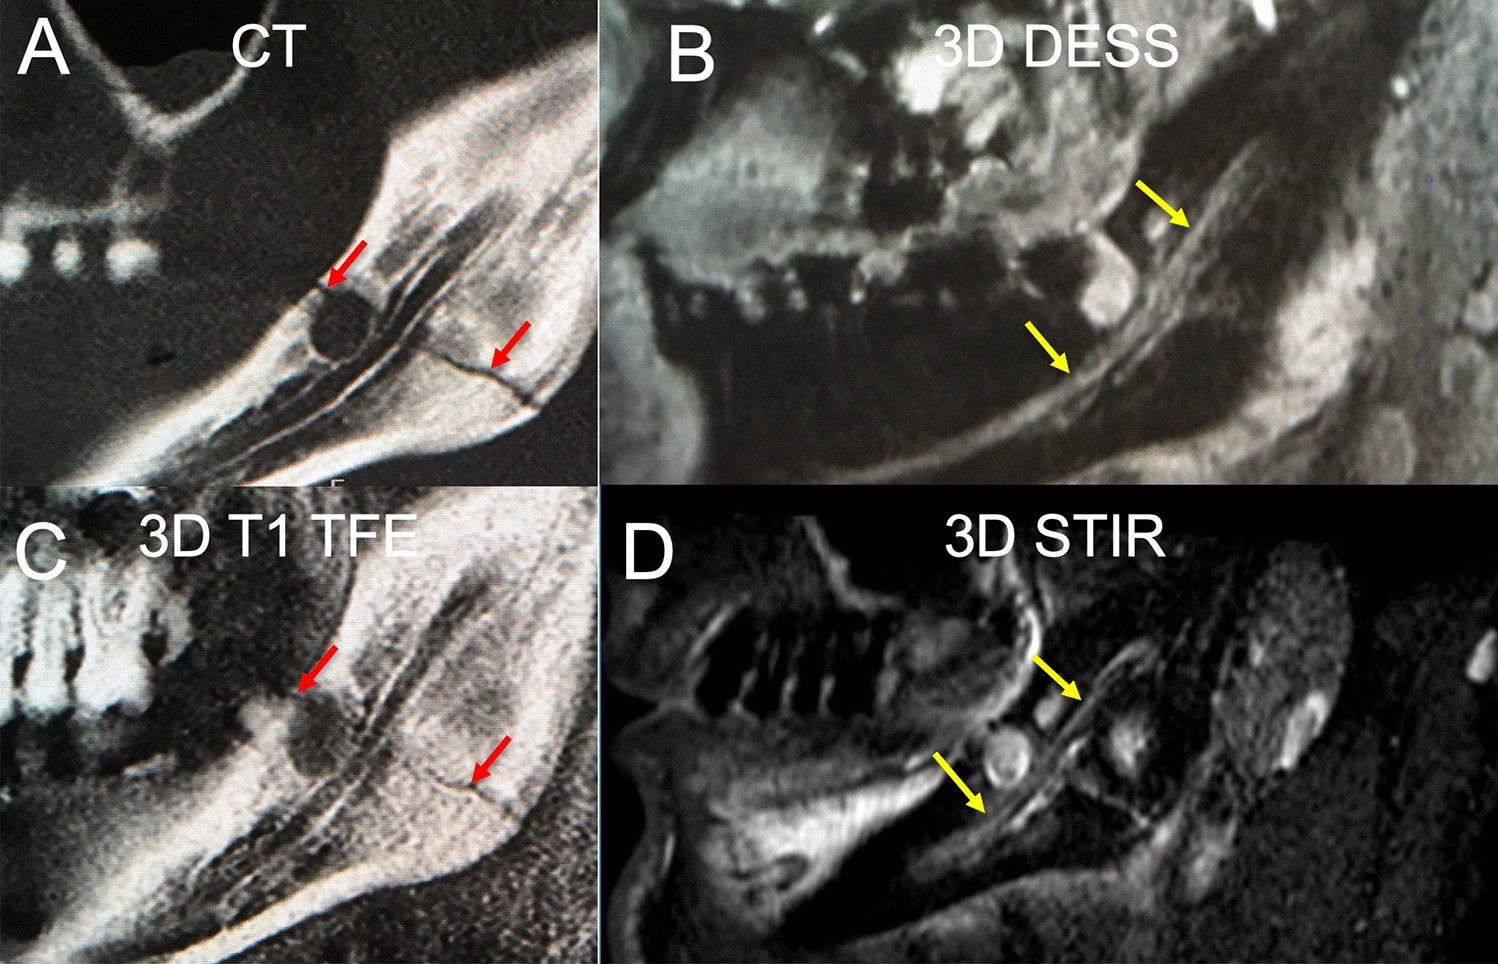

Figure 2

In this clinical case a slightly displaced mandible fracture is illustrated (red arrows). The CT (A) and the 3D T1 FFE sequence (C) revealed the osseous continuity disruption with involvement of the mandibular canal with comparable accuracy. However, no conclusions regarding the condition of the IAN can be drawn as it is not visualized sufficiently. The DESS sequence allows for precise depiction of the IAN (B). The STIR sequence shows an increase in signal intensity within the IAN as well as an enlarged nerve diameter (D). The nerve continuity is preserved (yellow arrows).